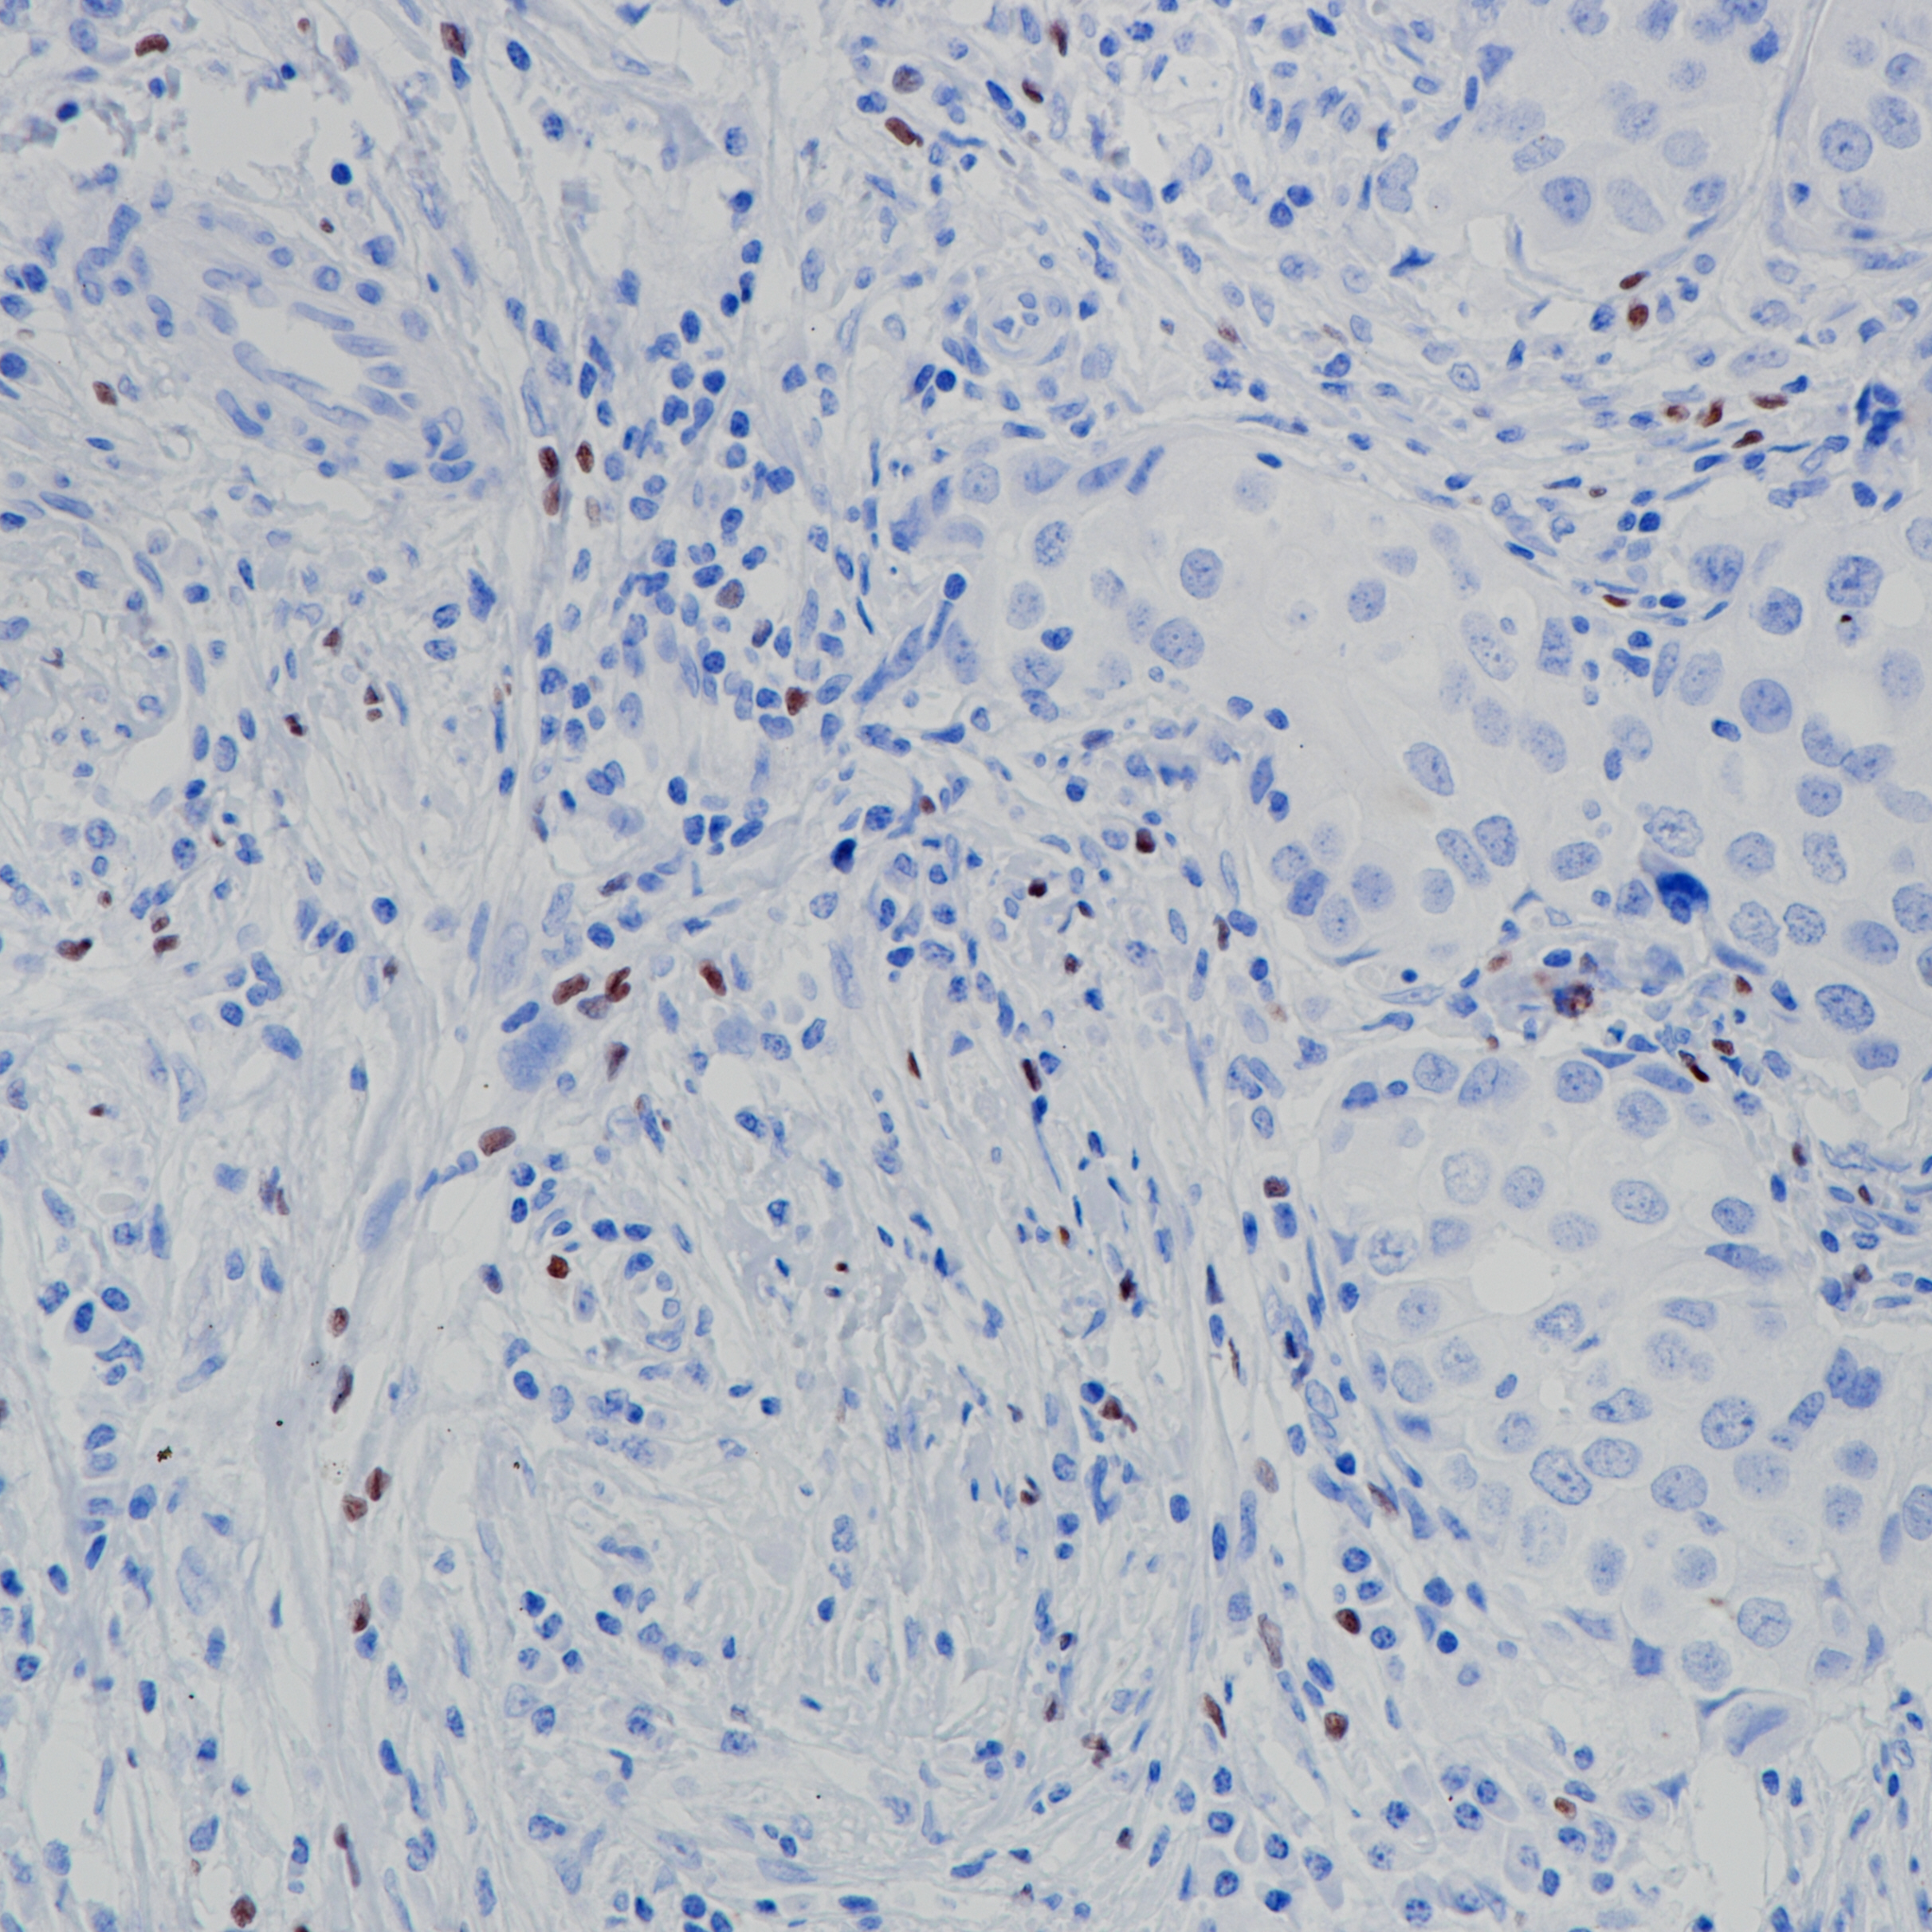

扁桃体 FoxP3(BP6166)染色

Forkhead box (Fox)蛋白是一个高度进化的保守转录因子家族,包含一个被称为Forkhead box或翼状螺旋DNA结合域的序列。FoxP亚家族有四个成员,FoxP1 - FoxP4。FoxP蛋白通常作为转录抑制因子。FOXP3在成人、T细胞白血病或淋巴瘤扁桃体中活化的T淋巴细胞中表达,在器官发育、免疫应答和癌症发病中发挥重要作用。

亚细胞定位

阳性对照